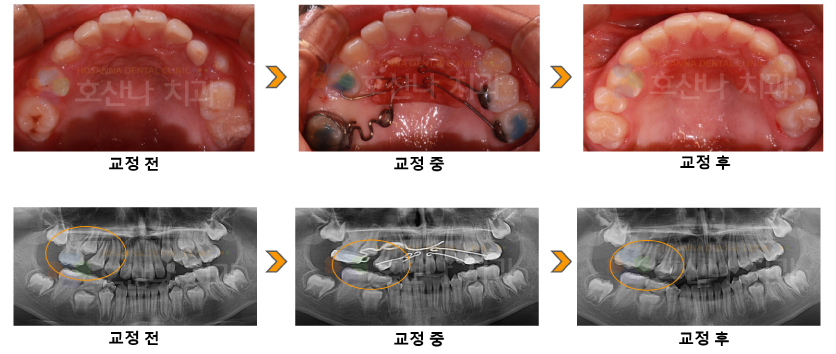

교정펜듈럼 교정 시술 증례

< 펜듈럼 교정 시술 증례 >

female / 10y/6m

#15 공간 부족해요

PI) #55 조기탈락으로 인해 #16 전방이동으로 #15 맹출 공간 부족함

본환자는  다른 부정교합은 없으나 #15 특정치아의 공간만 부족하여  영구치열 완성 전 펜듈럼을 통해 #16 을 후방이동시켜 #15번 공간을 확보해주었습니다.

이렇게 부정교합이 예상이 되는 경우 펜듈럼으로 미리 공간을 확보해주면 맹출이 잘 될 수 있습니다.

9m